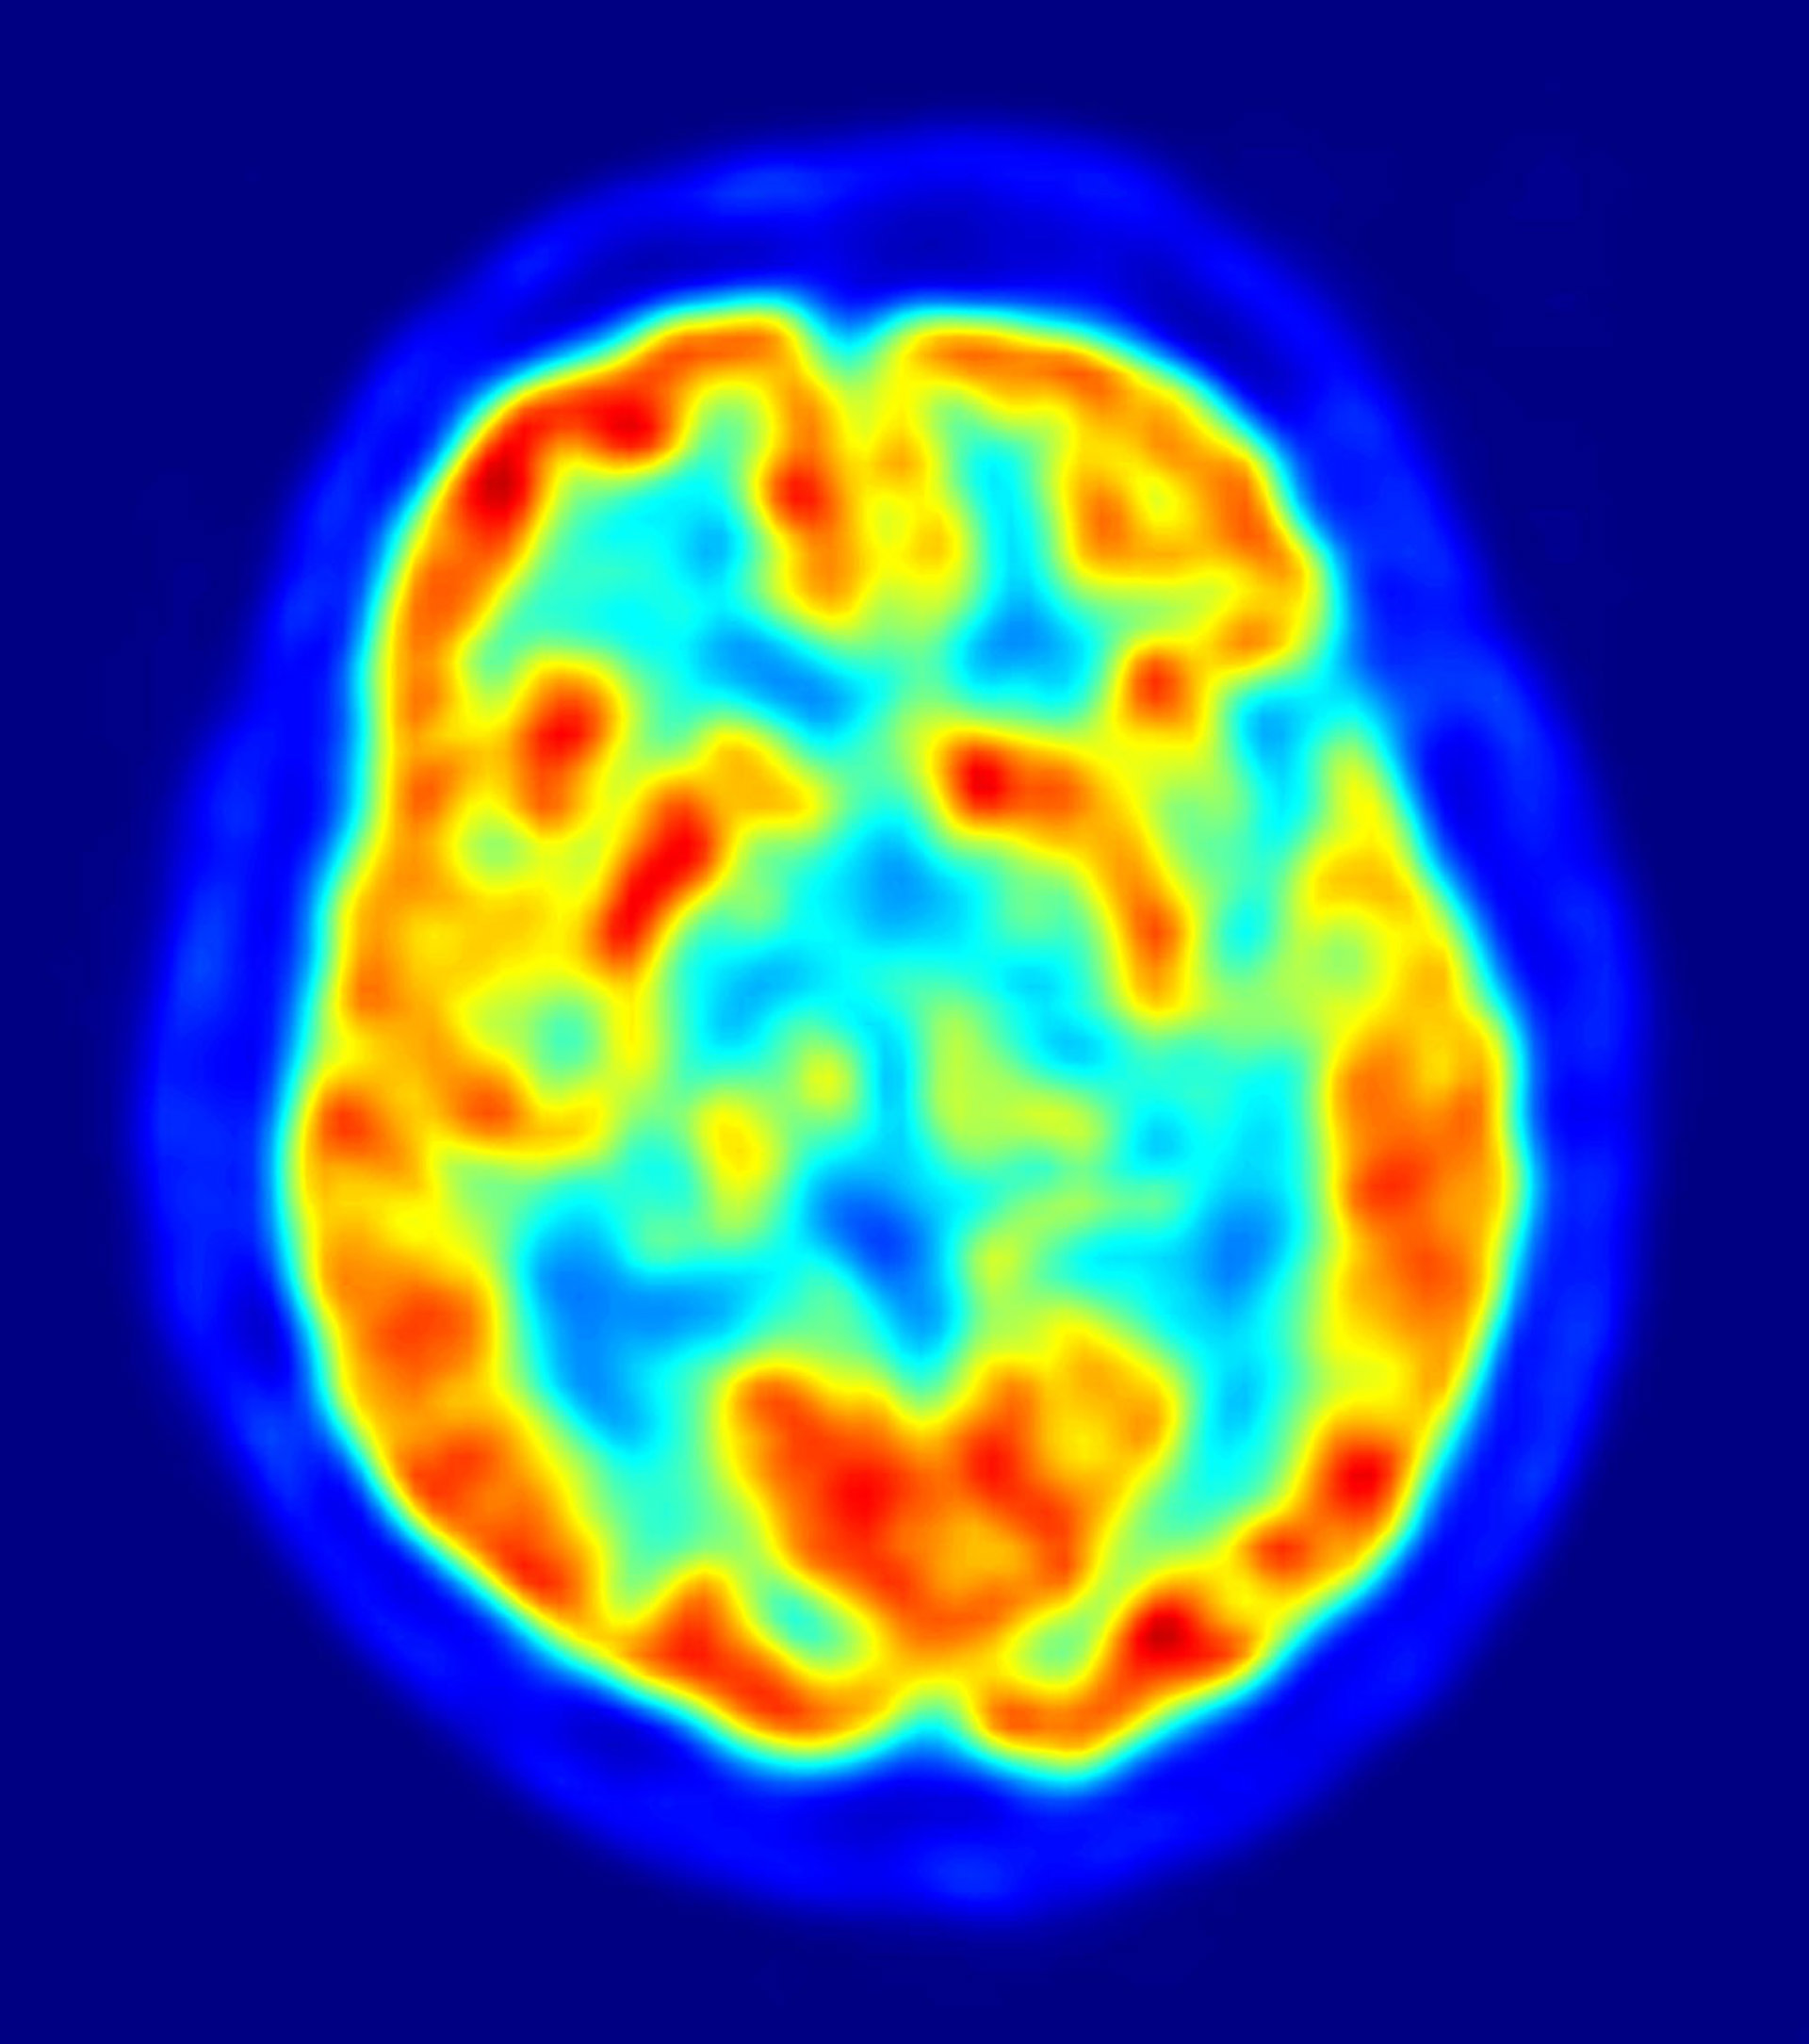

cerebro, recurso, neuronas